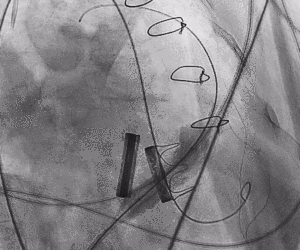

1.术中经股静脉入路,送入指引导管、导丝,成功跨瓣,建立导丝轨道。

2.进行预扩张。球囊打开时未见明显腰征,预扩张球囊顺利打开梗阻瓣膜。

3.经股静脉入路送入16F E-sheath可扩张导管鞘,随后送入SAPIEN 3球扩瓣1输送系统,由于肺动脉入路朝上走,无需调弯,顺利跨瓣,将SAPIEN 3球扩瓣送入预定位置。精准定位后,以160次/分快速起搏,并保证1:1完全夺获,缓慢释放瓣膜。术后超声检查结果显示即刻跨瓣压差从术前9mmHg降至3mmHg,顺利完成瓣膜释放,回撤导管、导丝。